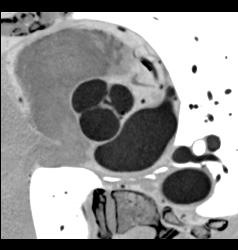

Normal Atrial Appendage